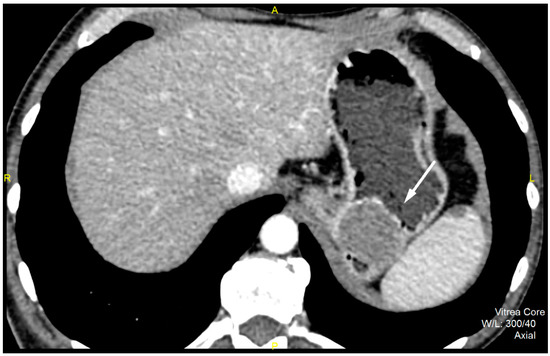

CT imaging features were analyzed as follows: maximal diameter in the axial slice and tumor structure, which was classified into cystic and solid/necrotic. The shape was depicted as regular or irregular. Tumor localization considered the body of the stomach, antrum or pyloric region. Mucosa was observed in two ways: intact/continuous or disrupted. Growth patterns were categorized as exophytic/mixed or endophytic. The degrees of enhancement of the solid part of tumor tissue were divided into weak, moderate or obvious enhancements. The presence of enlarged feeding or draining vessels (EFDV) was also recorded, as was the presence of metastasis in liver and other organs ( Figure 1, Figure 2 and Figure 3).

Multivariate analysis extracted the irregular shape (p = 0.006) and visible EFDV (p = 0.017) as the independent predictive CT features of HR GIST (Table 4). The ROC analysis revealed that multivariate linear regression model, which included the shape of the tumor together with the EFVD, achieved an AUC of 0.869 (0.770–0.967), with a sensitivity of 80.0%, specificity of 93.8% and accuracy of 87.1% in predicting the HR GIST (Figure 7).

According to our results, the diameter and cystic structure of the tumor, ill-defined margins, irregular shape, exophytic and mixed growth pattern, disrupted mucosal appearance and presence of enlarged feeding or draining vessels were found to be statistically significant factors for risk stratification in the univariate analysis. The logistic regression showed that only irregular tumor shape and presence of EFDV were independent predictors for high metastatic potential.

Figure 3. Contrast enhanced CT exam, coronal view, in a 49-year old female patient shows irregular shape and EFDV (white arrow) of a HR GIST.